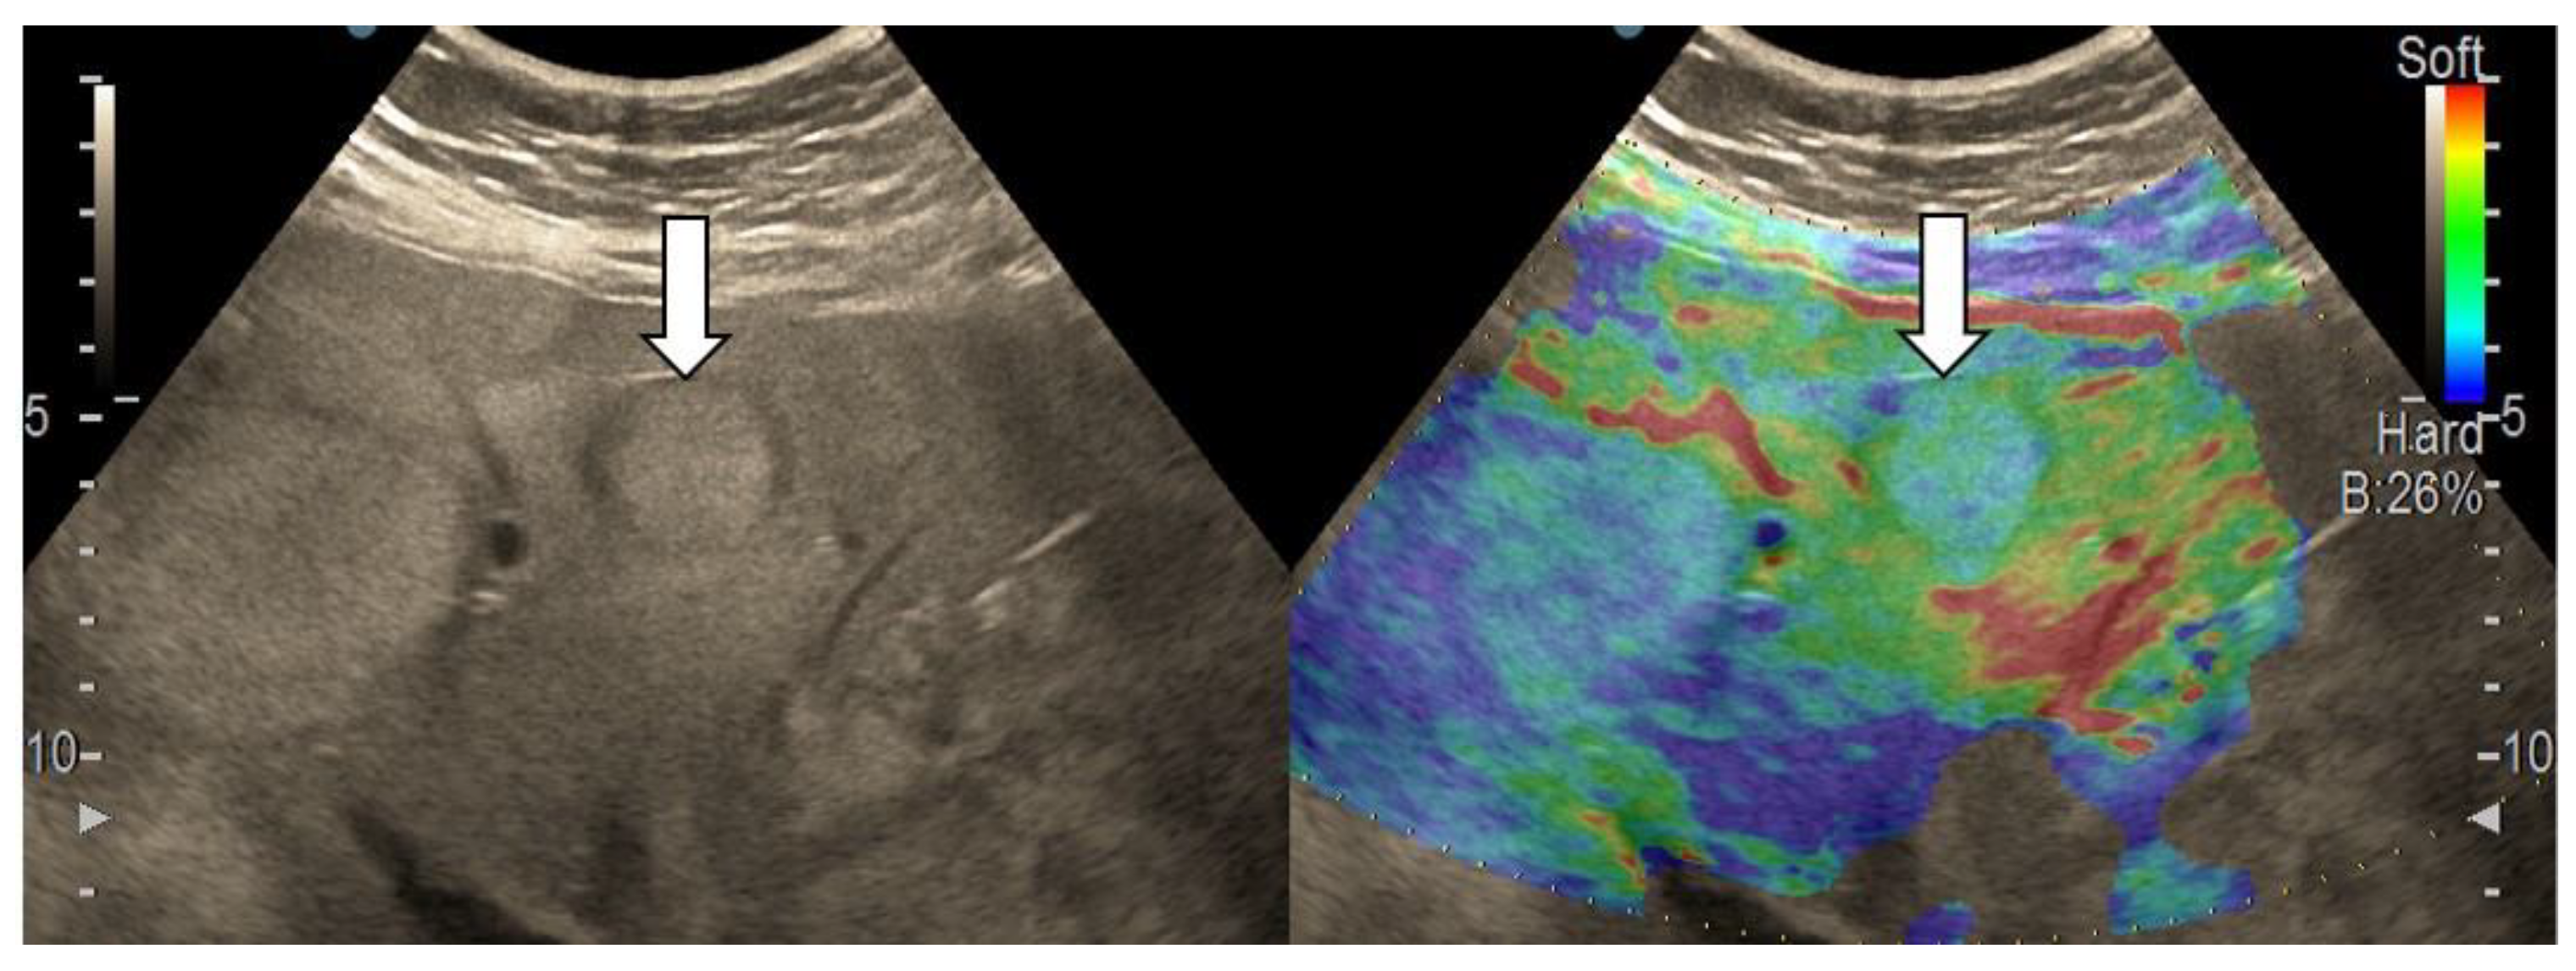

3.4. Real-Time Tissue Elastography

| Elasticity Type | Color Code |

|---|---|

| Type “a” | Homogenously green |

| Type “b” | Mosaic pattern with dominant green areas |

| Type “c” | Mosaic pattern with dominant blue areas |

| Type “d” | Homogenously light blue |

| Type “e” | Homogenously dark blue |

| RTE | Liver Adenoma | HMG | FNH | Complicated Liver Cyst | HCC | iCCA | Liver Metastases | Liver Lymphoma |

|---|---|---|---|---|---|---|---|---|

| Type “a” | 3 | 1 | ||||||

| Type “b” | 1 | 1 | 10 | 3 | 1 | |||

| Type “c” | 1 | 24 | 3 | 6 | ||||

| Type “d” | 1 | |||||||

| Type “e” | 5 | 3 | 1 |

| Sensitivity (95% CI) | Specificity (95% CI) | PPV (95% CI) | NPV (95% CI) | Accuracy (95% CI) |

|---|---|---|---|---|

| 79.55% | 89.29% | 92.11% | 73.53% | 83.33% |

| (64.70–90.20%) | (71.77–97.73%) | (79.85–97.17%) | (60.47–83.46%) | (72.70–91.08%) |